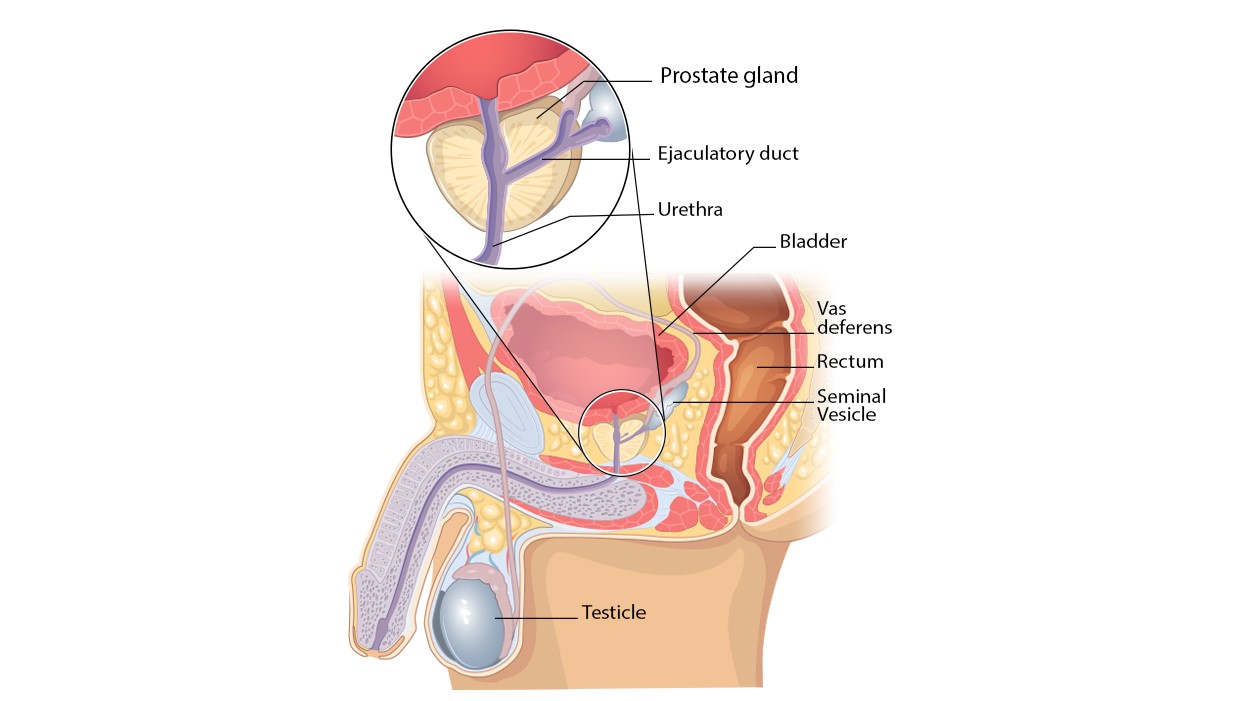

Where It Begins: Prostate Anatomy

The prostate gland is located below the urinary bladder and in front of the rectum. It surrounds part of the urethra, the tube that carries urine out of the body.

Functions of the Prostate:

Anatomy of the male pelvic region highlighting the prostate gland

Functions of the Prostate:

- Produces fluid that contributes to semen

- Supports normal urinary and reproductive function

Anatomy of the male pelvic region highlighting the prostate gland